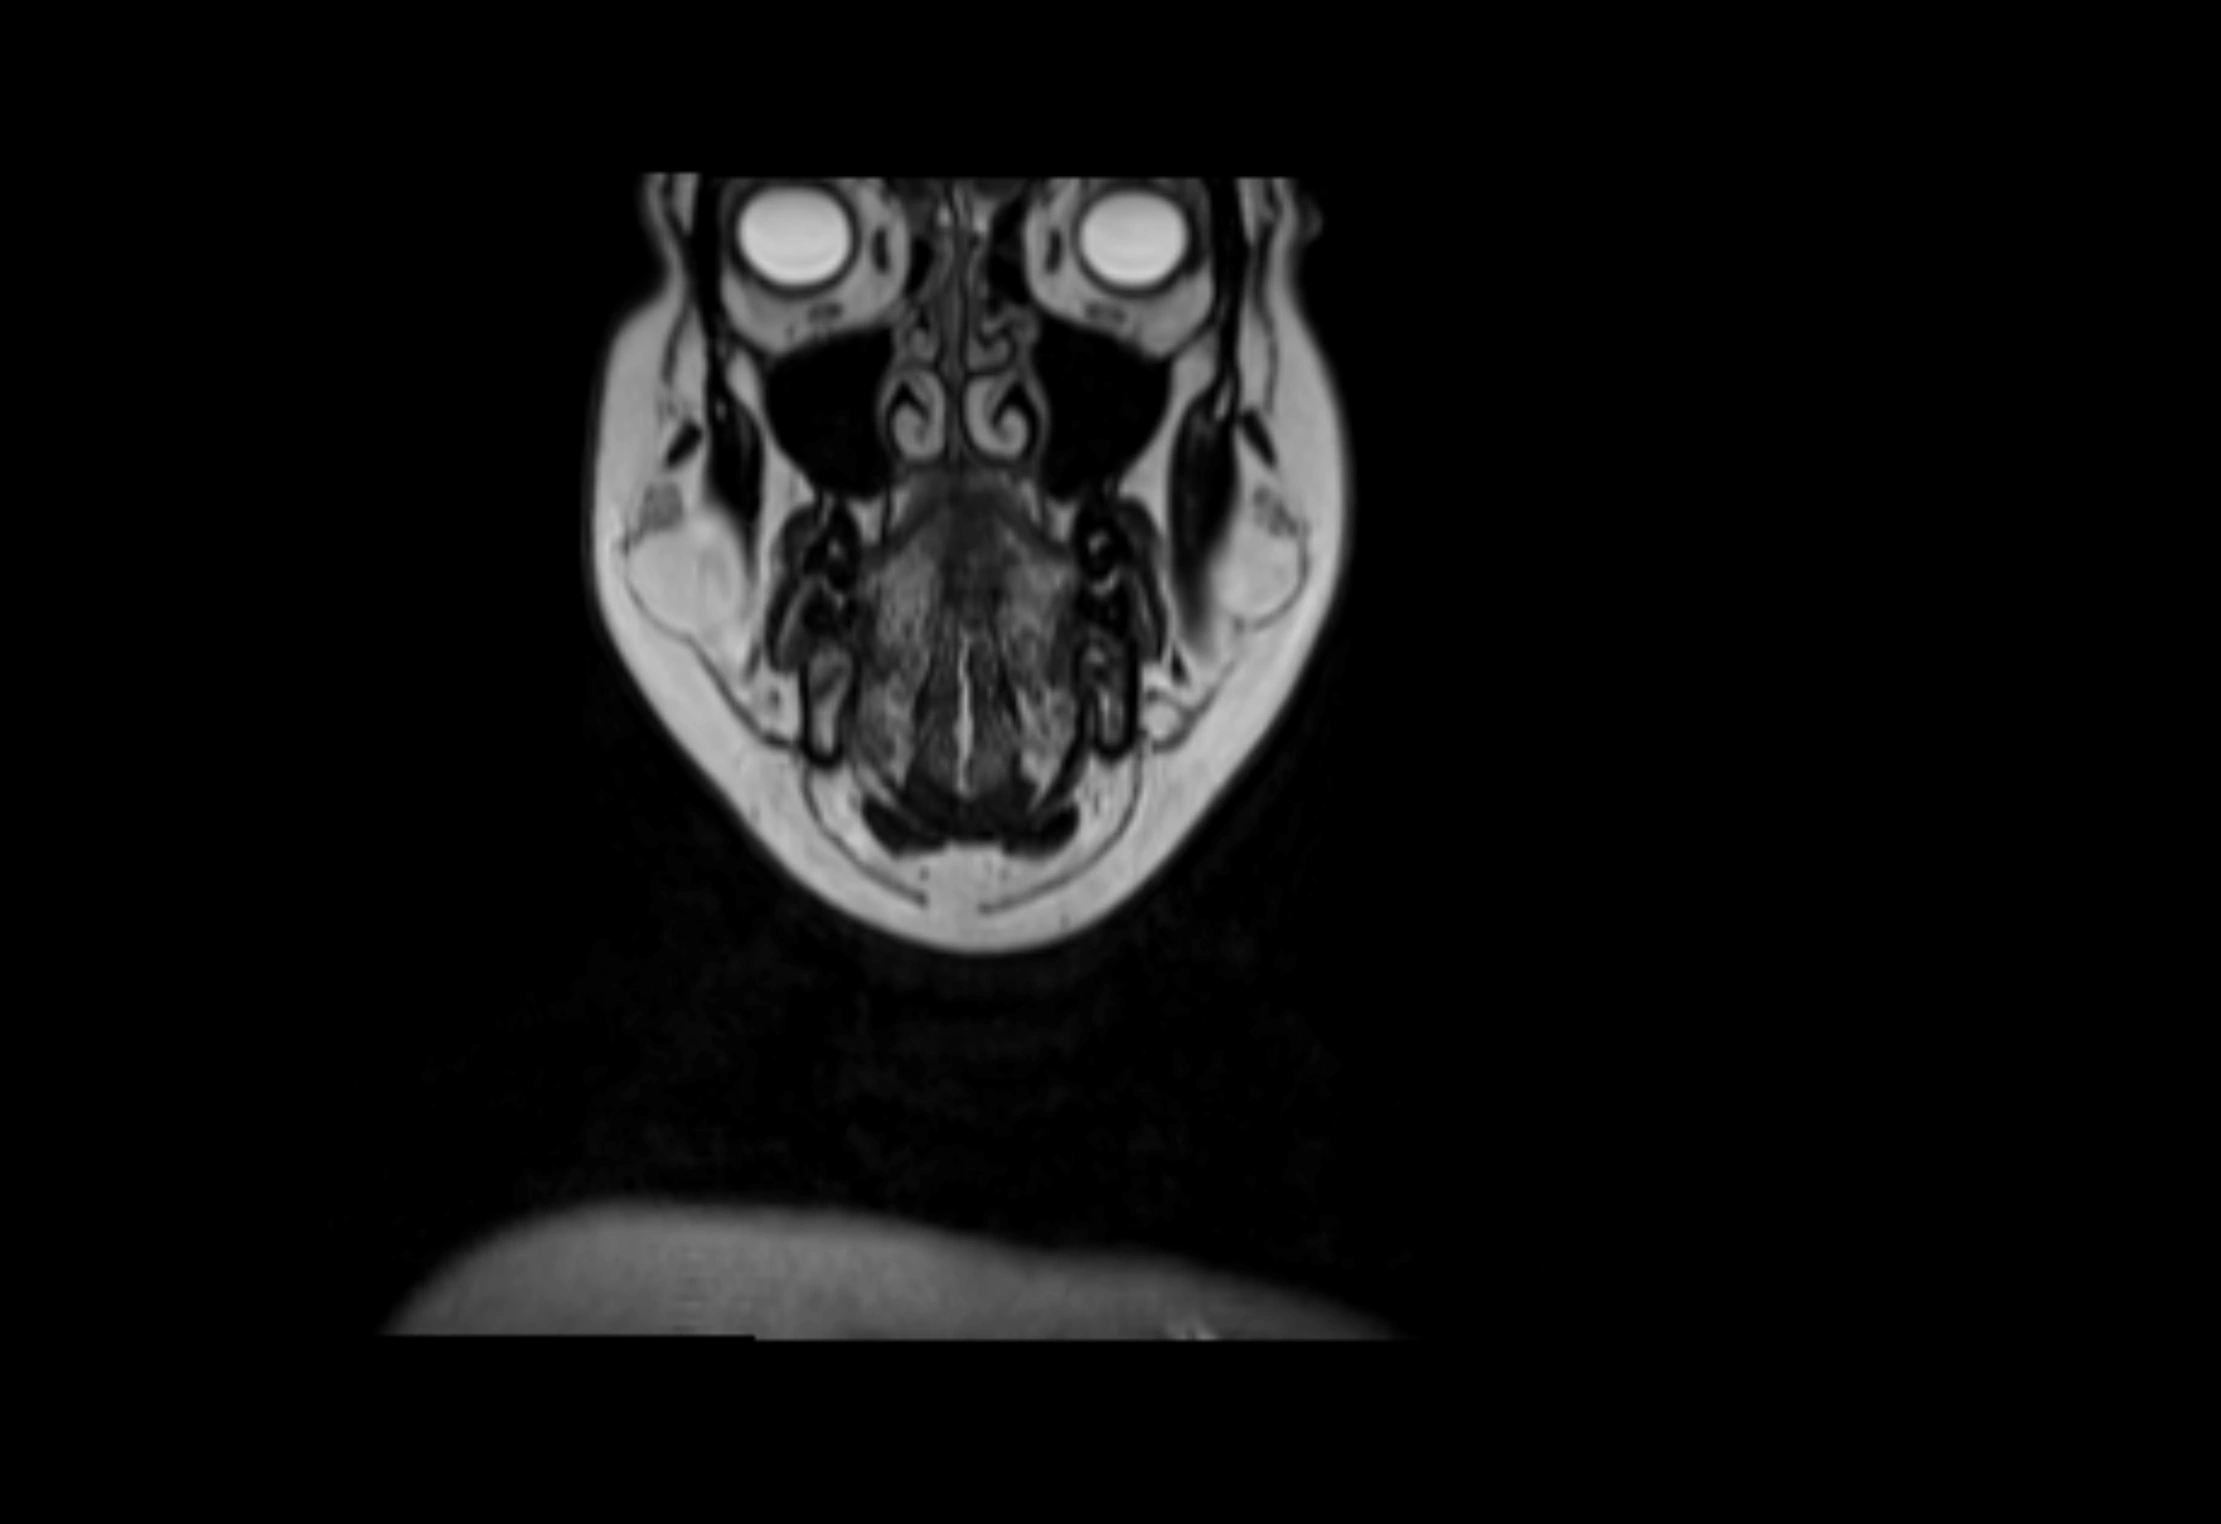

MRI Appearance

T1-weighted images:

• Normal accessory nodes appear as small, oval hypointense to intermediate signal structures within subcutaneous fat

• Surrounded by hyperintense fat, enhancing contrast for visualization

• Pathological nodes may appear enlarged or rounded, sometimes with cortical thickening

T2-weighted images:

• Nodes show intermediate signal, with surrounding fat bright

• Useful for detecting edema, inflammation, or infiltration

• Fatty hilum may appear slightly hyperintense relative to cortex